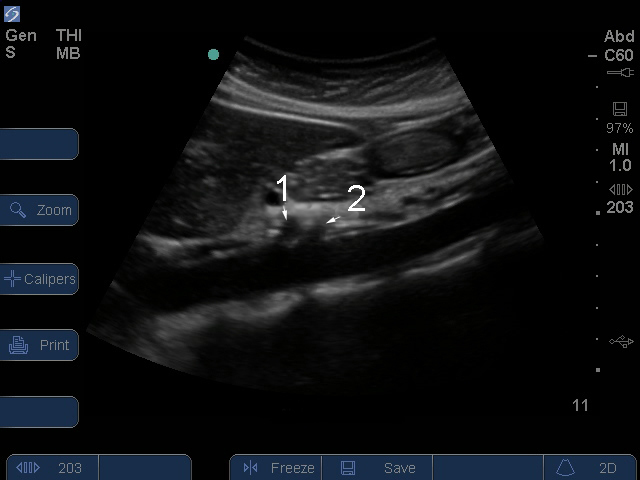

Aorta abdominal

1. Celíaca

2. Arteria mesentérica superior (AMS)